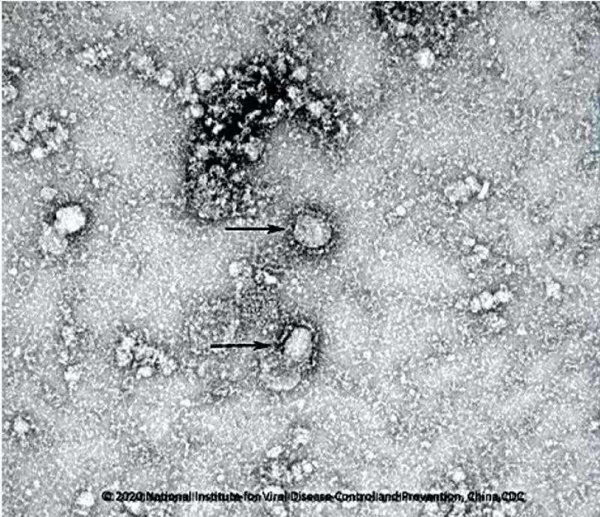

Bản sao của virus corona được lấy từ mẫu virus của bệnh nhân Úc nhiễm virus corona, nhập viện vào ngày 24/1.

Bản sao của virus corona được lấy từ mẫu virus của bệnh nhân Úc nhiễm virus corona, nhập viện vào ngày 24/1. Mẫu virus corona được nuôi trong phòng thí nghiệm, có thể sử dụng để phát hiện virus ở những bệnh nhân không có triệu chứng. Không những thế, Viện Lây nhiễm và Miễn dịch Peter Doherty cho biết đột phá này cũng sẽ giúp thử nghiệm bất cứ mẫu vắc xin nào nhằm đối phó với dịch bệnh đang hoành hành.

Cận cảnh virus corona.